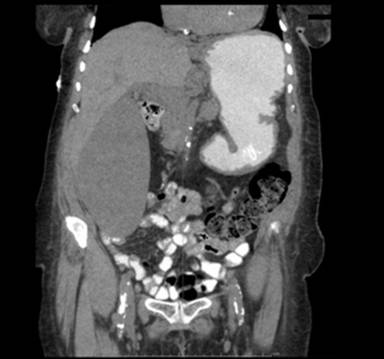

A seventy-six-year-old woman presented with chronic lower back pain and vague abdominal discomfort for one year. She was a known type-2 diabetic for twenty-five years with diabetic peripheral neuropathy, diabetic nephropathy (stage 3 chronic kidney disease) and a chronic diabetic foot ulcer. She was poorly compliant with taking her medications for her diabetes. During the past three years, she had noticed early post-prandial satiety as well as abdominal bloating. On physical examination, she had a non-tender palpable mass in the right upper quadrant of the abdomen. She was found to have elevated glycosylated hemoglobin level of 7.8% with normal ALT, AST, alkaline phosphatase, and total bilirubin. Total protein level was normal at 6.8 g/dL with low albumin of 3 g/dL. CT scan of abdomen was done with oral contrast due to a past history of iodine allergy (Figure 4). The gallbladder was 17.6 cm in its maximum length and 9.8 cm in width, with no gall stones or tumors. At the recommendation of the surgery service, the interventional radiologist performed a percutaneous cholecystostomy for decompression. Due to her poor nutritional status and existing co-morbidities, a plan for interval cholecystectomy was made in addition to plans for close clinic follow-up. The patient continued to have drainage from the cholecystostomy tube but declined to undergo surgery despite extensive counseling. She visited the outpatient clinic twice before she was lost to follow-up.

Figure 4. CT scan of the abdomen and pelvis with oral contrast, coronal view, showing a massively distended gallbladder with no visible gall stones or tumors. |